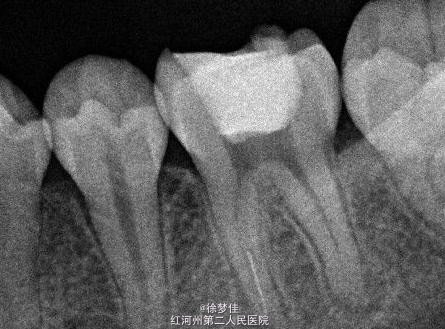

左下6近中根管断针X-P,断针长度约4MM, 根尖慢性炎症

插针确定断针根管,为近舌根管,插针有阻力,EDTA封存一周复诊。打开根管上部通路,根管大量清洗剂等冲洗,找到后,直接用超声根管搓15号带出断针。

操作时,注意工作长度,根管长度,断针长度,等等一切数据,需要科学客观的操作数据,摄片等,才能避免断针。